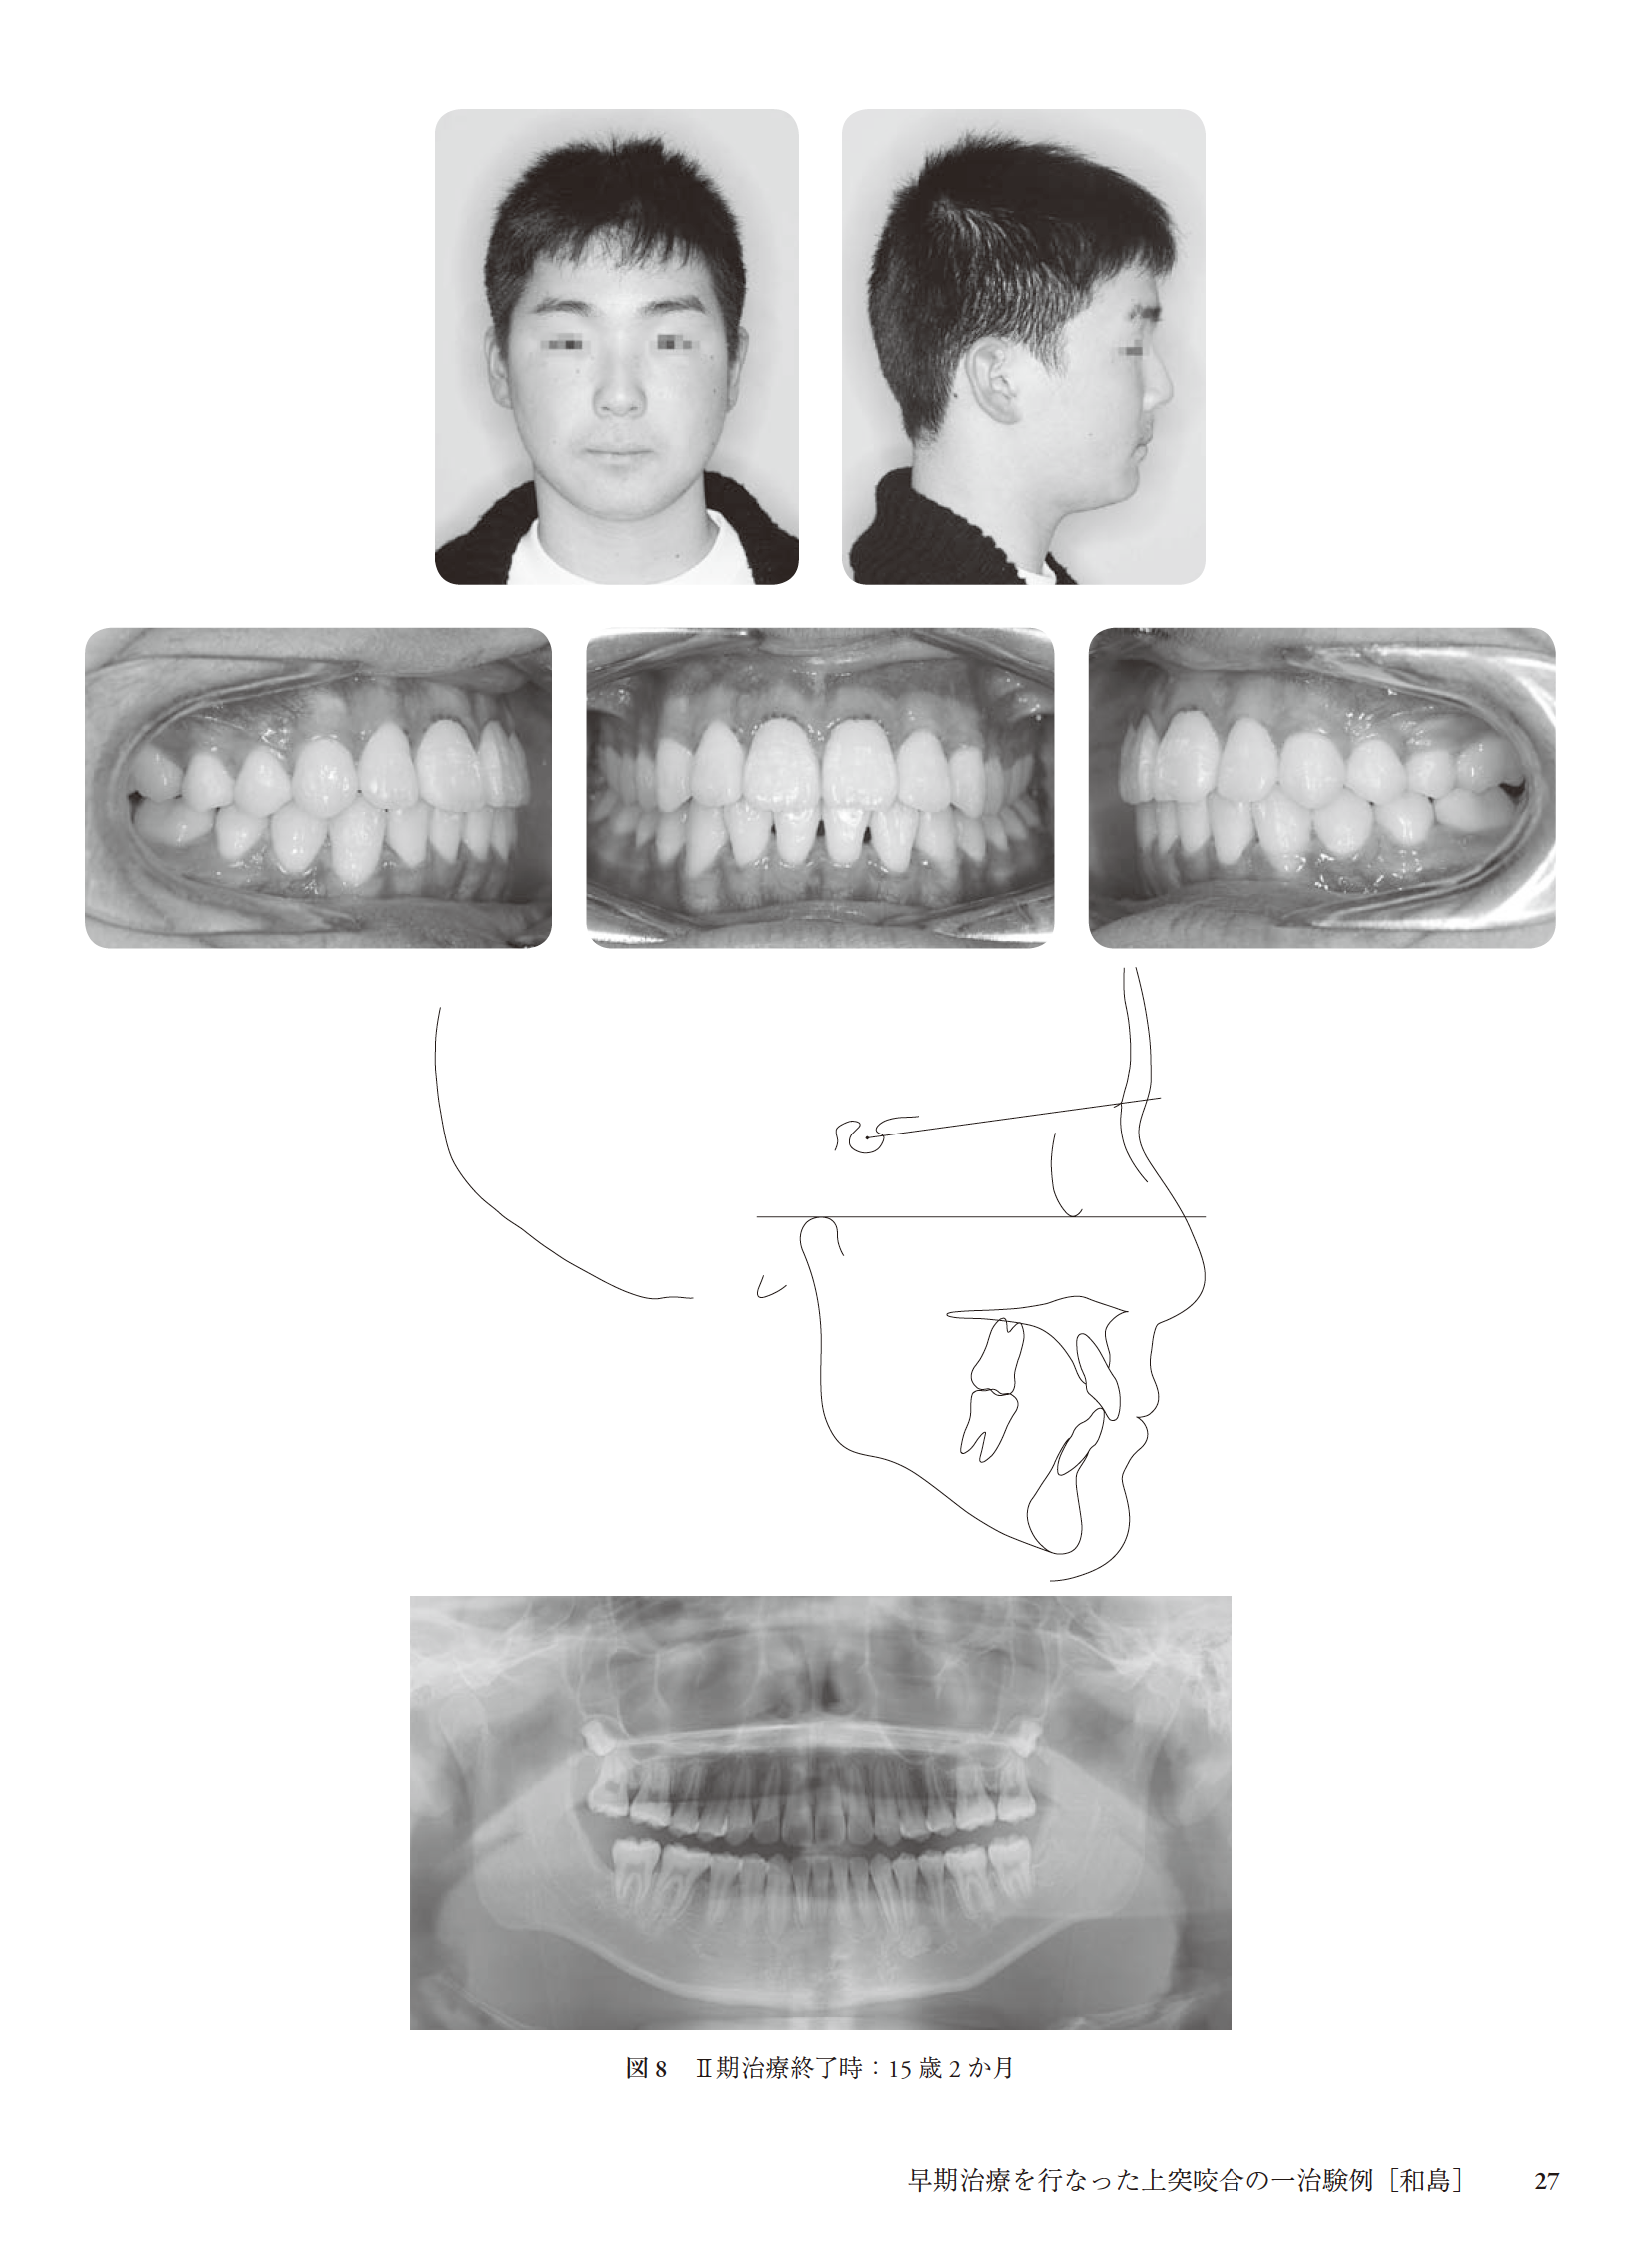

早期治療を行なった上突咬合の一治験例(和島)